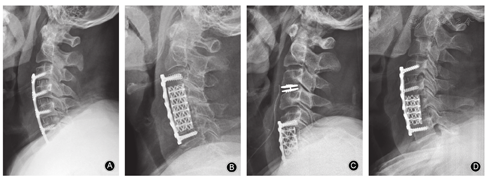

前入路术式包括:颈椎前路椎间盘切除椎间植骨融合术(anterior cervical discectomy and fusion,ACDF)、人工椎间盘置换术、颈椎前路椎体次全切除植骨融合术(anterior cervical corpectomy and fusion,ACCF)、Hybrid手术、颈椎前路椎间盘切除+椎体次全切除植骨融合术(ACDF+ACCF,图2)。

对≥3个节段的脊髓型颈椎病,传统观点认为手术虽然可以直接去除致压物及恢复前凸,但手术风险大、并发症多,如脊髓损伤、脑脊液漏、内植物脱出及假关节形成等并发症发生率高。但随着理念的更新和技术的进展,这种观点正在逐渐被改变。对大部分柔软的颈椎后凸畸形可以行单纯前路手术解决,即使是严重的畸形也能通过前路手术获得满意的矫形[18]。有文献报道对4个节段以前方致压为主的多节段脊髓型颈椎患者行前路手术治疗,获得了良好的临床疗效[19]。另外ACDF治疗脊髓型颈椎病具有显著临床疗效,且颈椎局部矢状位序列保持相对稳定,手术前后颈椎矢状位参数变化与临床疗效具有一定的相关性[20]。因此对致压≥3个节段、脊髓前方受压为主,尤其是合并重度后凸畸形(>40°以上)的多节段脊髓型颈椎病,由于后路椎管成形术后脊髓不能有效后移,可能会影响神经症状的改善。只要不合并连续性长节段后纵韧带骨化或宽基底的后纵韧带骨化、多节段黄韧带肥厚或先天性椎管狭窄,且术者熟练掌握颈椎前方解剖结构、多节段椎间隙减压和固定技术,可以选择前路手术,只是手术时间相对延长,不一定增加并发症的发生率(图3)。术式最好以ACDF或ACDF+ACCF为主,如减压节段较多,或椎体次全切后钛网过长,为防止钛网塌陷,选择混合手术减压方式可达到有效减压、固定及矫形的目的[21]。